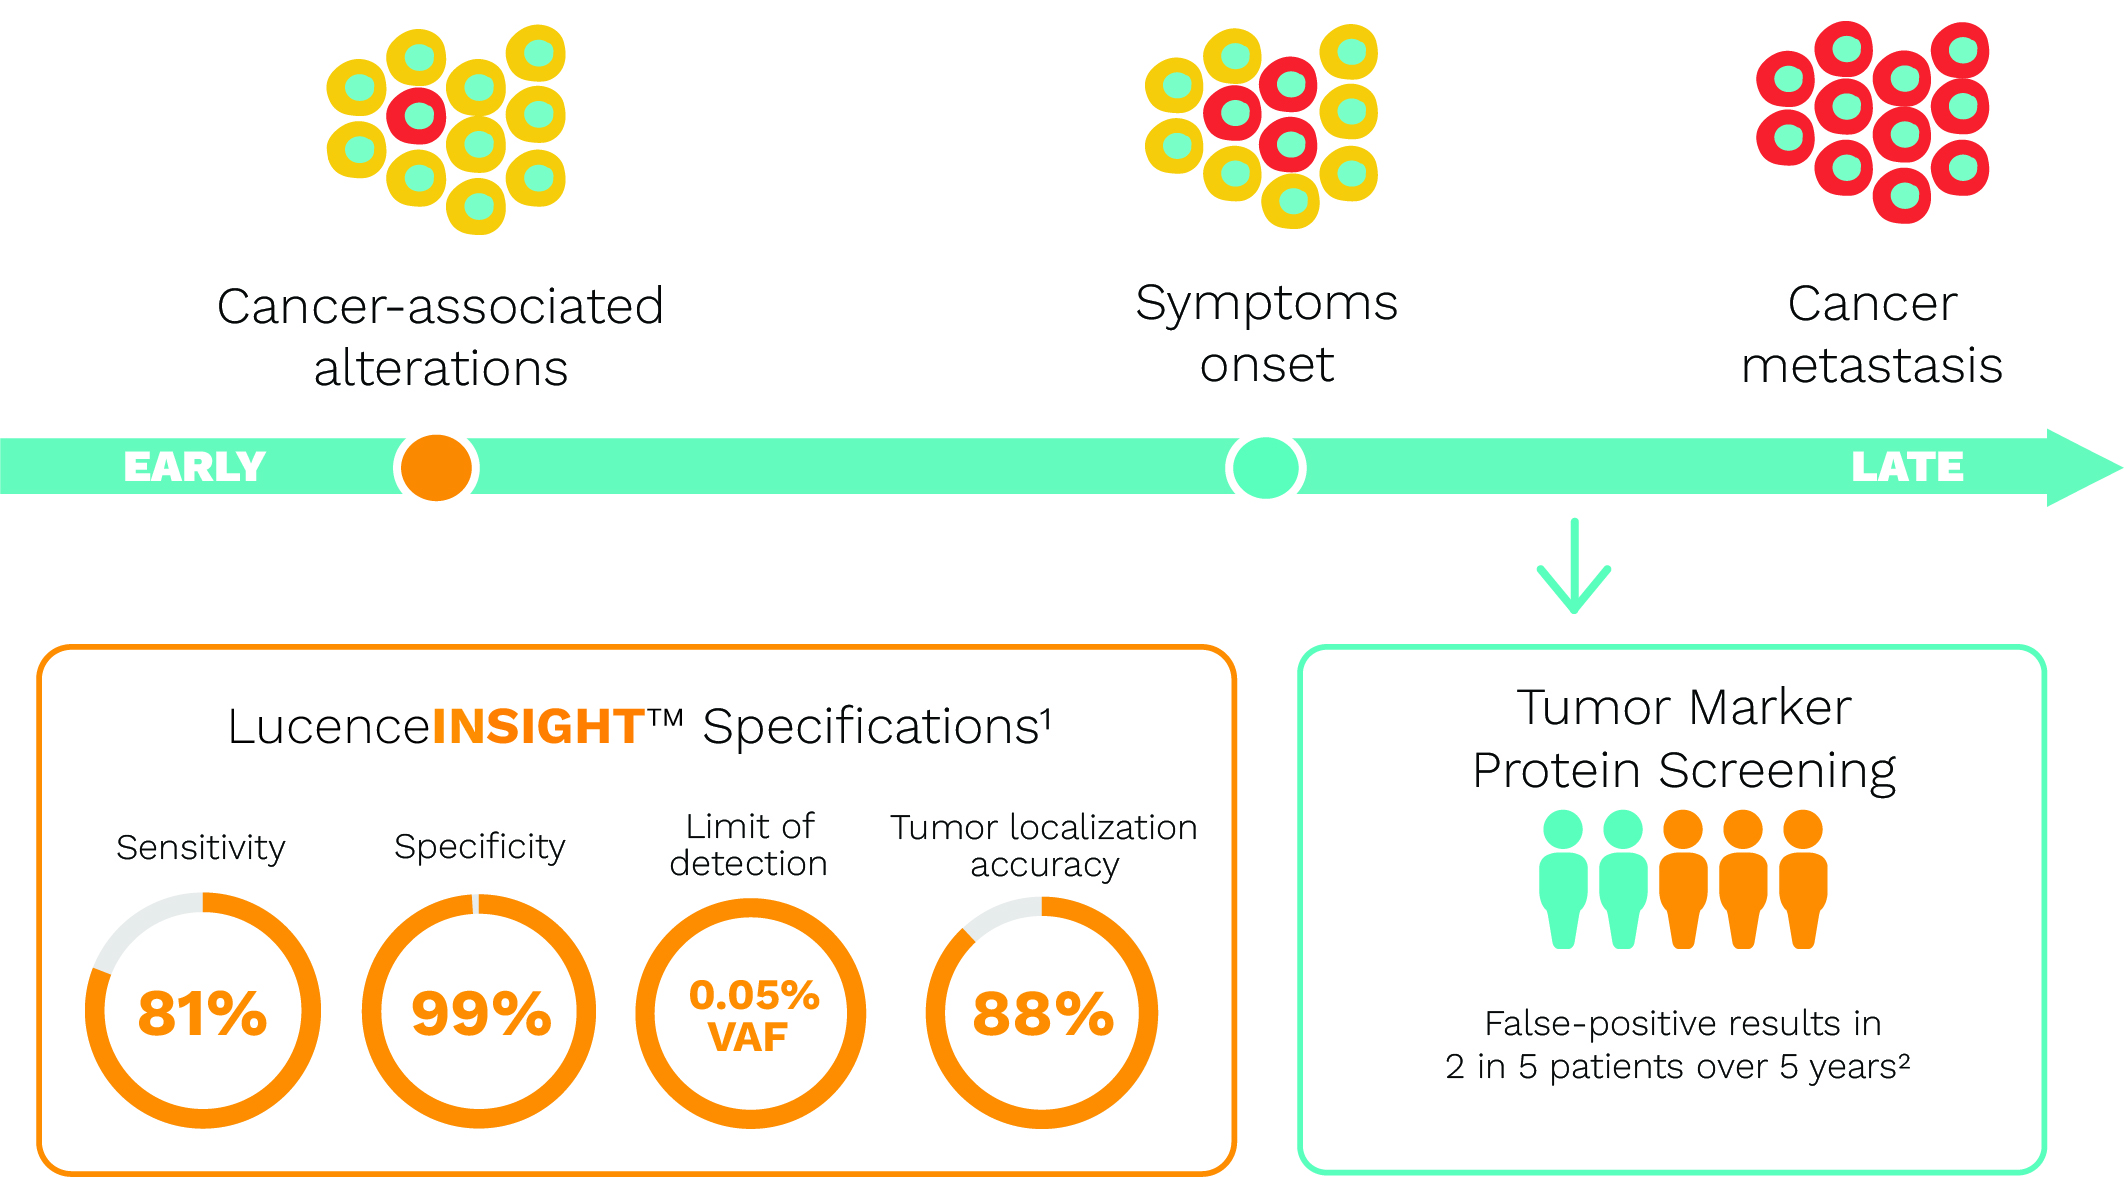

路胜因思康™ 以低假阳性率筛查癌症。

在2023 年对 264 名真实的无症状患者进行了前瞻性研究,结果显示路胜因思康TM的阳性预测值为 100% (PPV)。3

在2024 年对 601 份患者样本进行回顾性研究,结果显示其灵敏度达到 81%,特异性达到 99%。1